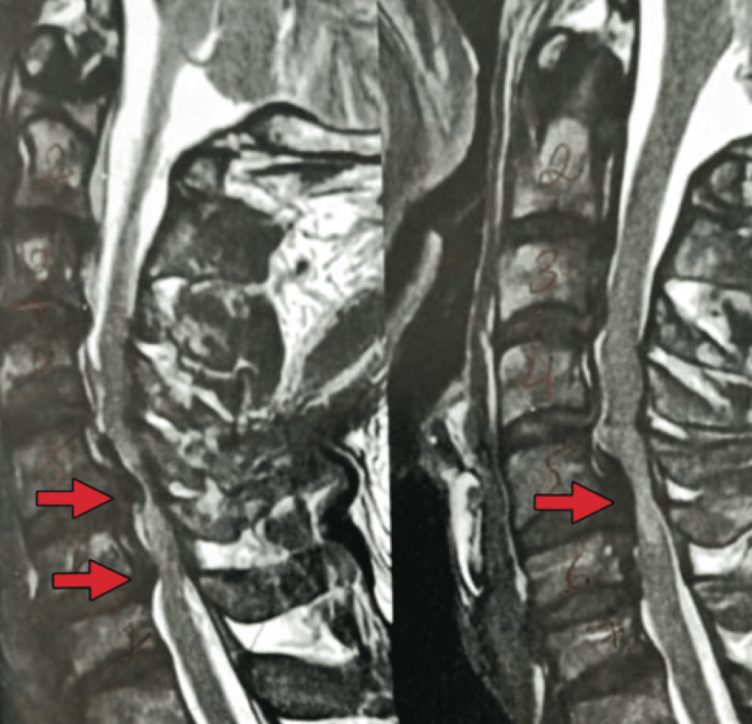

Cervical stenosis is a degenerative condition that causes compression of the spinal cord and nerve roots, resulting in neurological symptoms such as pain, weakness, and loss of motor and sensory function. Surgical treatment, such as spinal decompression, is indicated for severe cases, as untreated compression may lead to irreversible damage.

Intraoperative neurophysiological monitoring (IONM) has proven essential for patient safety, allowing early detection of neurological changes and enabling immediate intervention. This article discusses the importance of IONM in severe cervical stenosis surgeries, highlighting preventive measures to minimize neurological damage. We report the case of a 57-year- old patient with severe cervical stenosis associated with myelopathy.